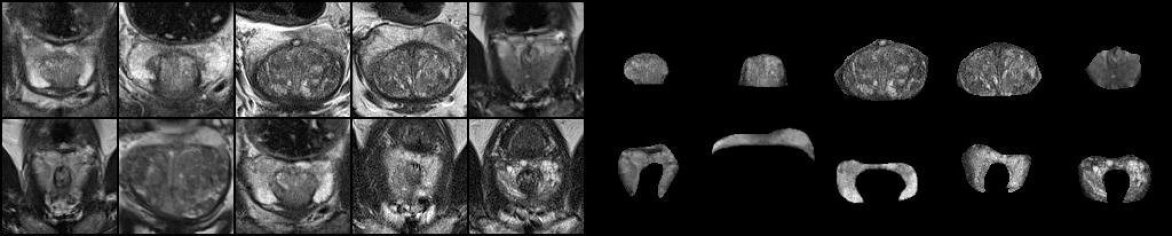

For the out-of-distribution bio-medical image dataset, we assemble three sets of radiological images featuring 6 organ/lesion concepts. These images are sourced from three public MRI segmentation datasets: heart myocardial infarction (Lalande et al., 2020), prostate segmentation (Antonelli et al., 2022), and Brain Tumor Segmentation (BraTS) (Menze et al., 2014). Each dataset includes per-concept masks. For biomedical images, we request a human or a machine, such as GPT-4, to similarly describe each image using one adjective and one noun for each pertinent concept. For both natural and biomedical datasets, we collected 40 images for each concept. Figure 43 and Figure 44 gives some examples of the prepared datasets.

![]() |

| hamster (top) - watermelon (bottom) | cavity (top) - myocardium (bottom) |

| bananas (top) - basket (bottom) | transition (top) - peripheral (bottom) |

| cactus (top) - ball (bottom) | tumour (top) - edema (bottom) |